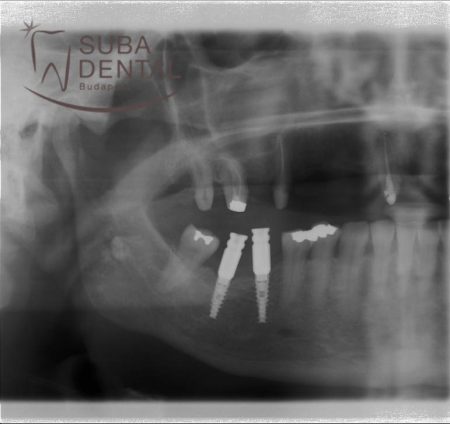

Zártkanalas lenyomatvételi fejek az implantátumokba helyezve kontroll röntgenfelvételen